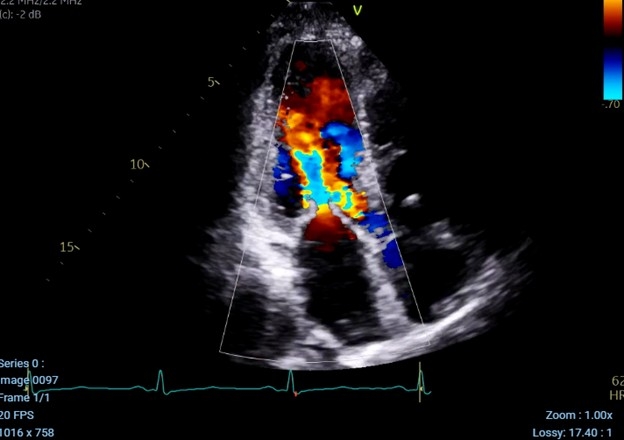

A 66-year-old woman presented to cardiology clinic for evaluation of dyspnea with exertion and leg swelling. Comorbidities included chronic kidney disease and a history of jejunal neuroendocrine tumor (NET) with prior resection and recent recurrence complicated by peritoneal carcinomatosis. A transthoracic echocardiogram was obtained at time of recurrence (1 year prior to presentation) and showed mild mitral regurgitation (MR), mild bi-atrial enlargement, moderate tricuspid regurgitation (TR), and mild aortic regurgitation (AR) with preserved ejection fraction.

In clinic, physical exam showed jugular venous distention with prominent V waves and a systolic and diastolic murmur. Transthoracic echocardiogram (TTE) demonstrated severe TR, moderate to severe AR, moderate MR, severe pulmonary valve regurgitation, and a right to left shunt with enlarged right ventricle and reduced function.

Patient was diagnosed with left and right carcinoid heart disease involving all 4 cardiac valves in the setting of a patent foramen ovale (PFO). After multidisciplinary discussion, surgical intervention was recommended. She underwent successful cardiopulmonary bypass with mitral valve replacement, aortic valve, pulmonary valve replacement, and tricuspid valve replacement in addition to closure of PFO. She did well postoperatively and was stable for dismissal from the hospital after 12 days.